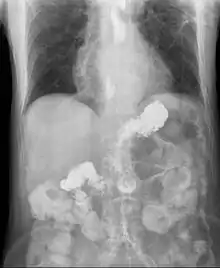

![]() ارتجاع معدي مريئي | |